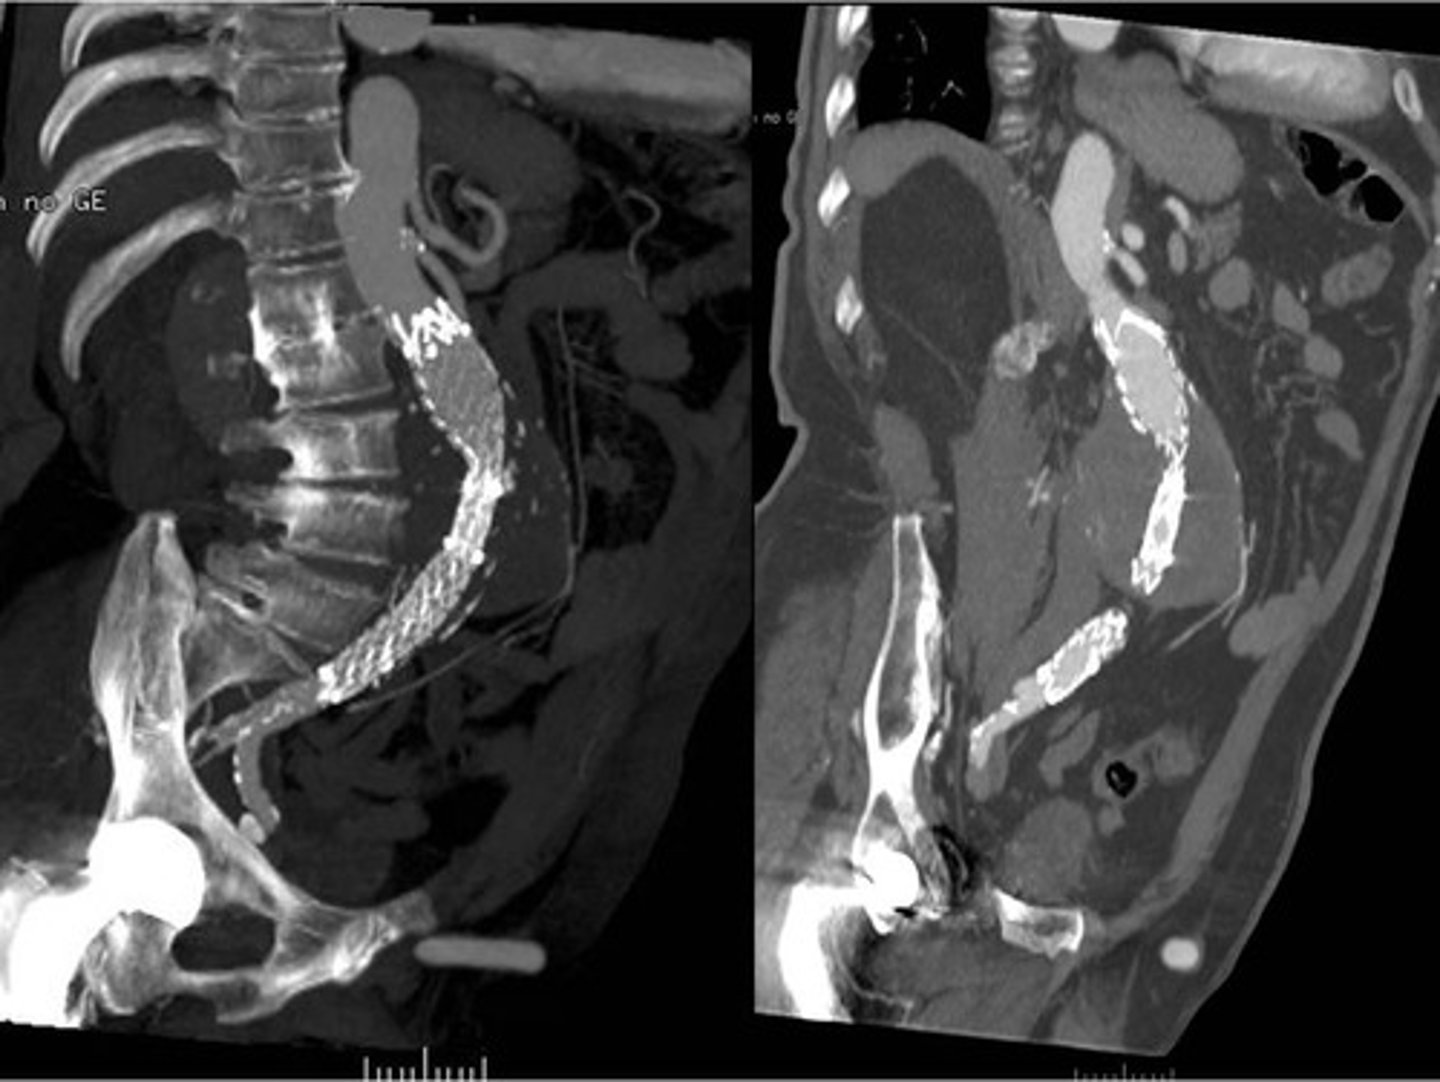

Abdominal aortic aneurysm on CT

endostent placement due to AAA